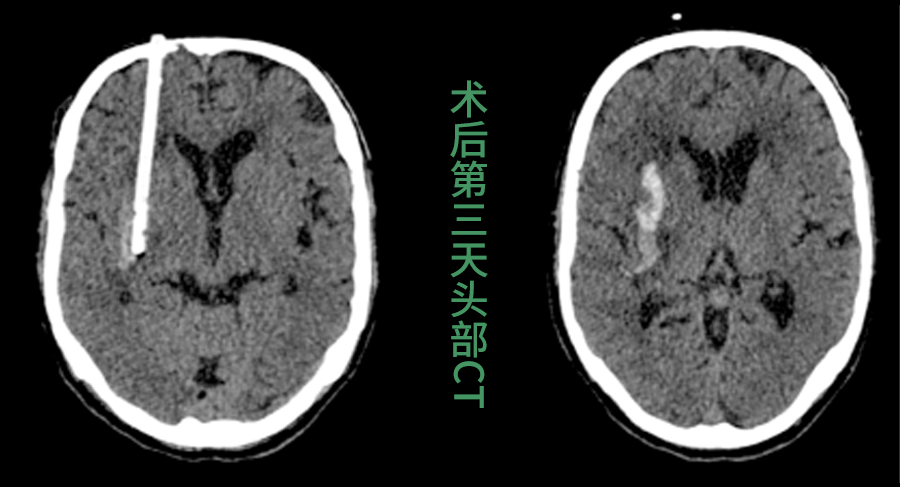

脑出血起病急、致死致残率高,及时清除血肿是拯救生命的关键。传统的穿刺引流术虽属微创,但医生只能在二维CT影像的指引下,凭借临床经验徒手进行穿刺。这个过程存在一定的不确定性,如同在没有导航的复杂路况中行车,难以确保每次都能“一击即中”。

3.精准引导,一击即中:手术中,这枚特殊的“GPS”导板稳固贴合在患者头部,为手术穿刺针提供精确的进针角度和深度通道,穿刺导管沿此通道进入,直达血肿中心,实现毫米级的精准定位。